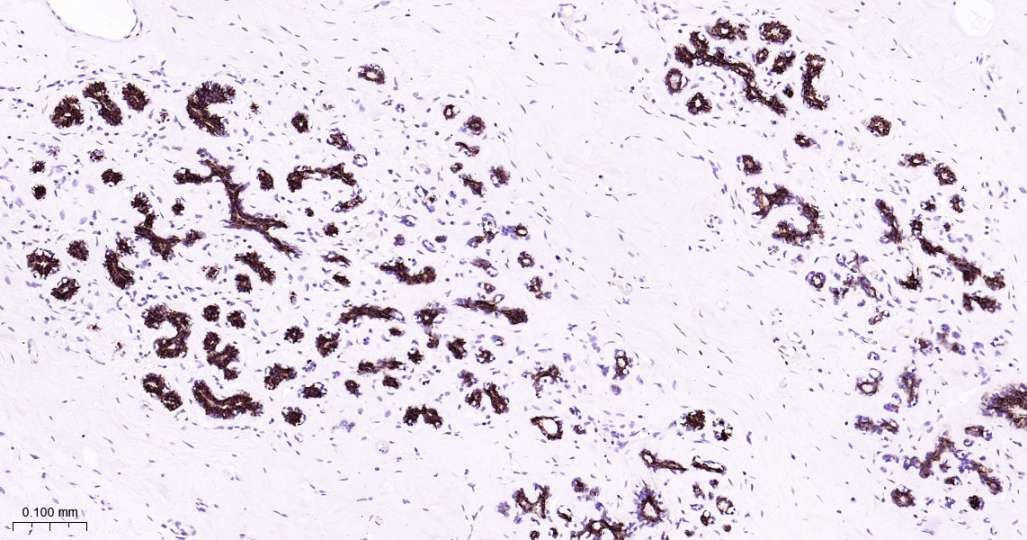

Immunohistochemical analysis of paraffin embedded Human prostate tissue slide using IHC0604H (Human Keratin 7 Kit).

Immunohistochemical analysis of paraffin embedded Human ovarian cancer tissue slide using IHC0604H (Human Keratin 7 Kit).

Immunohistochemical analysis of paraffin embedded Human cervical cancer tissue slide using IHC0604H (Human Keratin 7 Kit).

Immunohistochemical analysis of paraffin embedded Human liver tissue slide using IHC0604H (Human Keratin 7 Kit).

Immunohistochemical analysis of paraffin embedded Human kidney tissue slide using IHC0604H (Human Keratin 7 Kit).

Immunohistochemical analysis of paraffin embedded Human breast cancer tissue slide using IHC0604H (Human Keratin 7 Kit).

Immunohistochemical analysis of paraffin embedded Human mammary gland tissue slide using IHC0604H (Human Keratin 7 Kit).